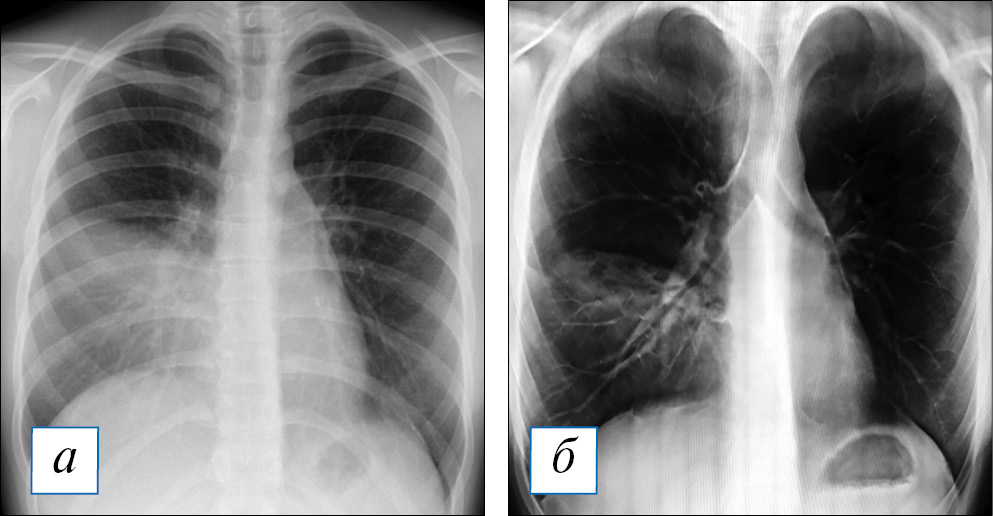

Рис. 1. Результаты лучевого обследования пациентки К., 16 лет, на 6-е сут заболевания. Первично рентгенографически (а) диагностирована верхнедолевая пневмония. По результатам томосинтеза (б, в), выполненного также на 6-е сут заболевания, зона затемнения захватывает всю нижнюю долю левого легкого; подозрение на формирование деструктивных очагов в сегментах 4 и 5 слева стало поводом для пересмотра (расширения) схемы эмпирической антибактериальной терапии. / Fig. 1. Results of X-ray examination of the patient K., 16 years old, 6th day of the onset of disease. Primary radiografically was diagnosed upper lobe pneumonia (a). According to the results of tomosynthesis (б, в), also performed on the 6th day of the disease, the zone of the blackout captures the entire lower lobe of the left lung; destructive foci in segments 4 and 5 of the left lung (under suspicion). These data were the reasons for the revision (expansion) of the empirical antibacterial therapy.